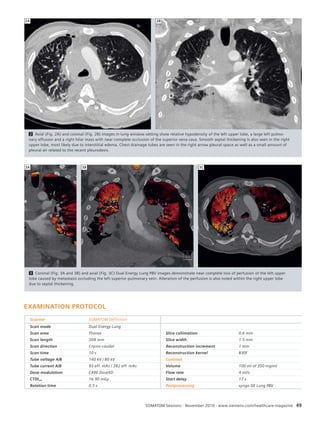

56 Dual Source, Dual Energy CT:

Improvement of Lung Perfusion

Within 5 Hours in a Patient With

Acute Pulmonary Embolism

58 Differentiation of Pulmonary Emboli

and Their Effect on Lung Perfusion

Determined With a Low-Dose Dual

Energy Scan